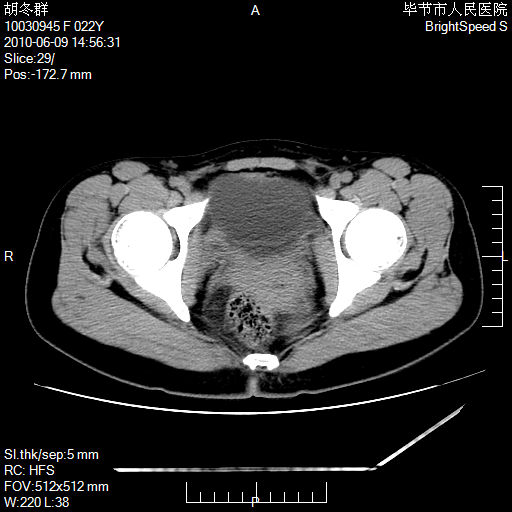

患者23岁,发现腹部包块3月。

左侧卵巢囊腺瘤或囊腺癌

盆腔内囊性占位性病变;考虑左侧卵巢囊腺瘤。

有分隔、壁薄,支持考虑左侧卵巢囊腺瘤。

左侧卵巢浆液性囊腺瘤。

支持考虑左侧卵巢囊腺瘤;宫腔积液。

有分隔、壁薄,支持考虑左侧卵巢囊腺瘤。排尿后,膀胱缩小,由于重力作用,肿块下移就到了膀胱位置,很好理解。